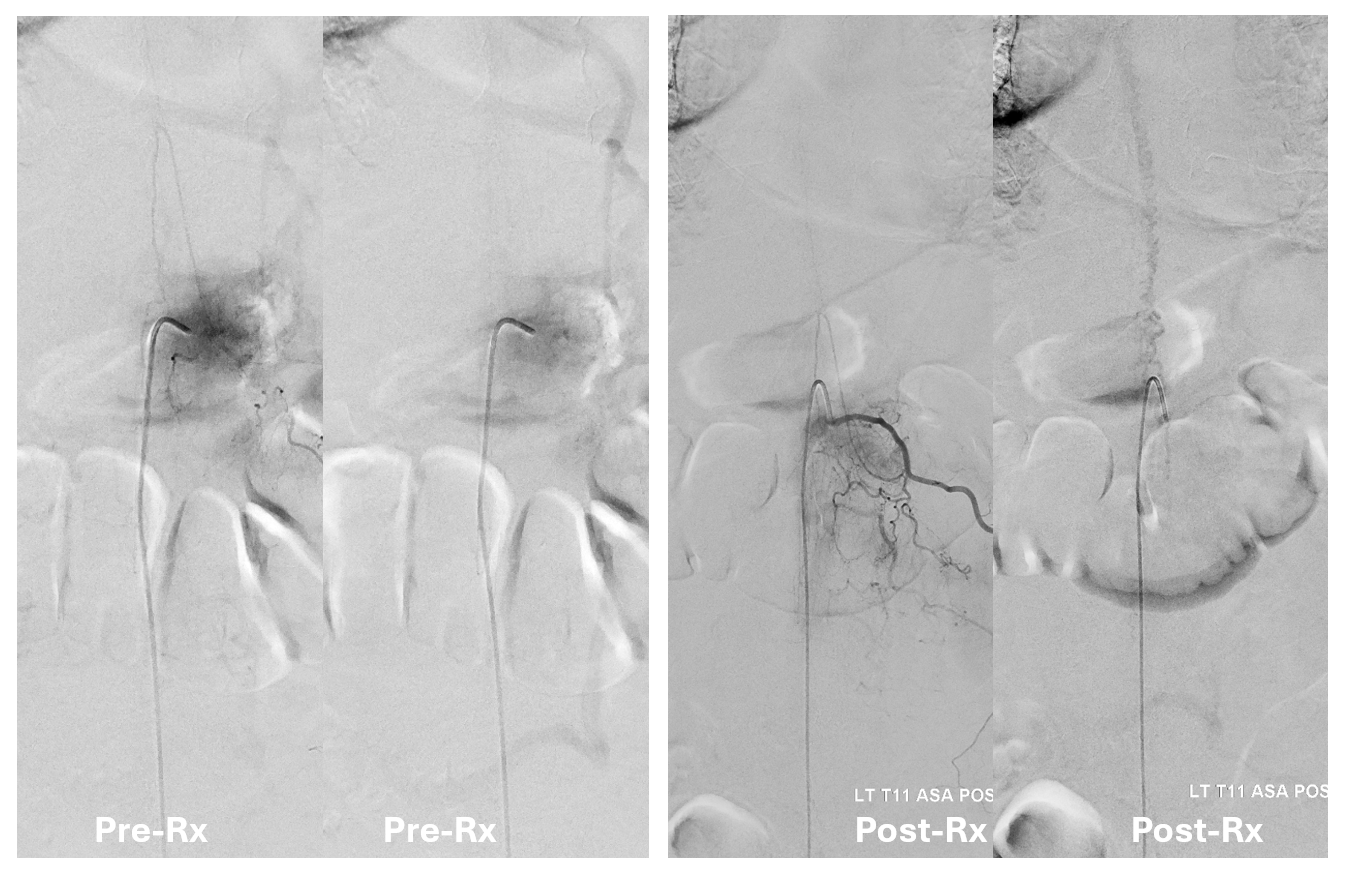

Key image here — injection of Adamkiewicz now shows return of the prodigal veins to the venous phase of the cord. Image on left also shows the now liberated basket.

pre and post Rx ASA views side by side

It is critical to understand cord venous drainage in post-dural fistula patients is never normal. The radicular veins are still missing. This may in part be responsible for the incomplete clinical recovery, although the main reason is probably cord damage before fistula occlusion.